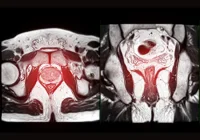

MRI protocols for suspected localised prostate cancer show notable variation across UK Trusts. Most centres use multiparametric MRI, incorporating T2-weighted imaging, diffusion-weighted imaging and dynamic contrast-enhanced sequences, while a smaller proportion employ biparametric MRI without contrast. The balance between these approaches reflects differing views on the value of contrast, efficiency and image quality. Radiologists using multiparametric MRI expressed mixed willingness to switch to biparametric protocols if future guidance recommended such a change, indicating ongoing debate rather than consensus.